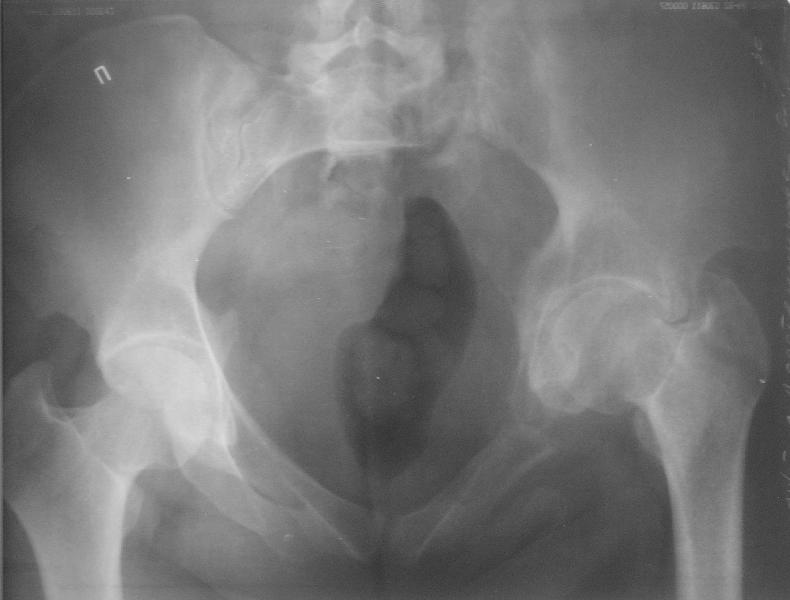

Прооперировали молодую девушку 32 лет спустя 9 мес после травмы. Имелся стойкий болевой синдром, неопороспособность левой н/конечности, моторные и сенсорные нарушения в левой голени и стопе, патологическая подвижность левой половины таза. Первым этапом закрыто в аппарате исправили деформацию ( в течении 2,5 нед). Вторым закрытое введение илиосакральных винтов в крестец (канюллированные 7,2 мм Chm) + туннелизация зоны псевдоартроза спицама Киршнера, реконструкция передних отделов таза, накостный остеосинтез . Аппарат частично демонтирпован, оставлена "передняя рама" После устранения деформации отмечен регресс неврологической симптоматики, уменьшение болевого синдрома. Интересующие вопросы: 1. Прогноз для сращения псевдоартроза крестца. 2. сроки нагрузки весом левой половины таза. Буду очень признателен за ваши мнения по этому поводу.A female 32 y.o. admitted to our unit 9 months after initial injury with pain, inability to bear weight at the left lower limb, sensor and motor disturbances in the left foot and tibia, with mobility of the left hemipelvis.At first closed reduction was performed by an external fixator within 2,5 weeks. After correction her pain decreased and some neurological progress was achieved. Now two iliosacral screws 7,2 mm were inserted, and anterior lesion was fixed by a plate. External fixator was partially unmounted, only anterior frame left in place.Images attached.How would you evaluate chances of healing of the sacrum with the current position?When would you allow weight-bearing of the left leg?THX in advance.